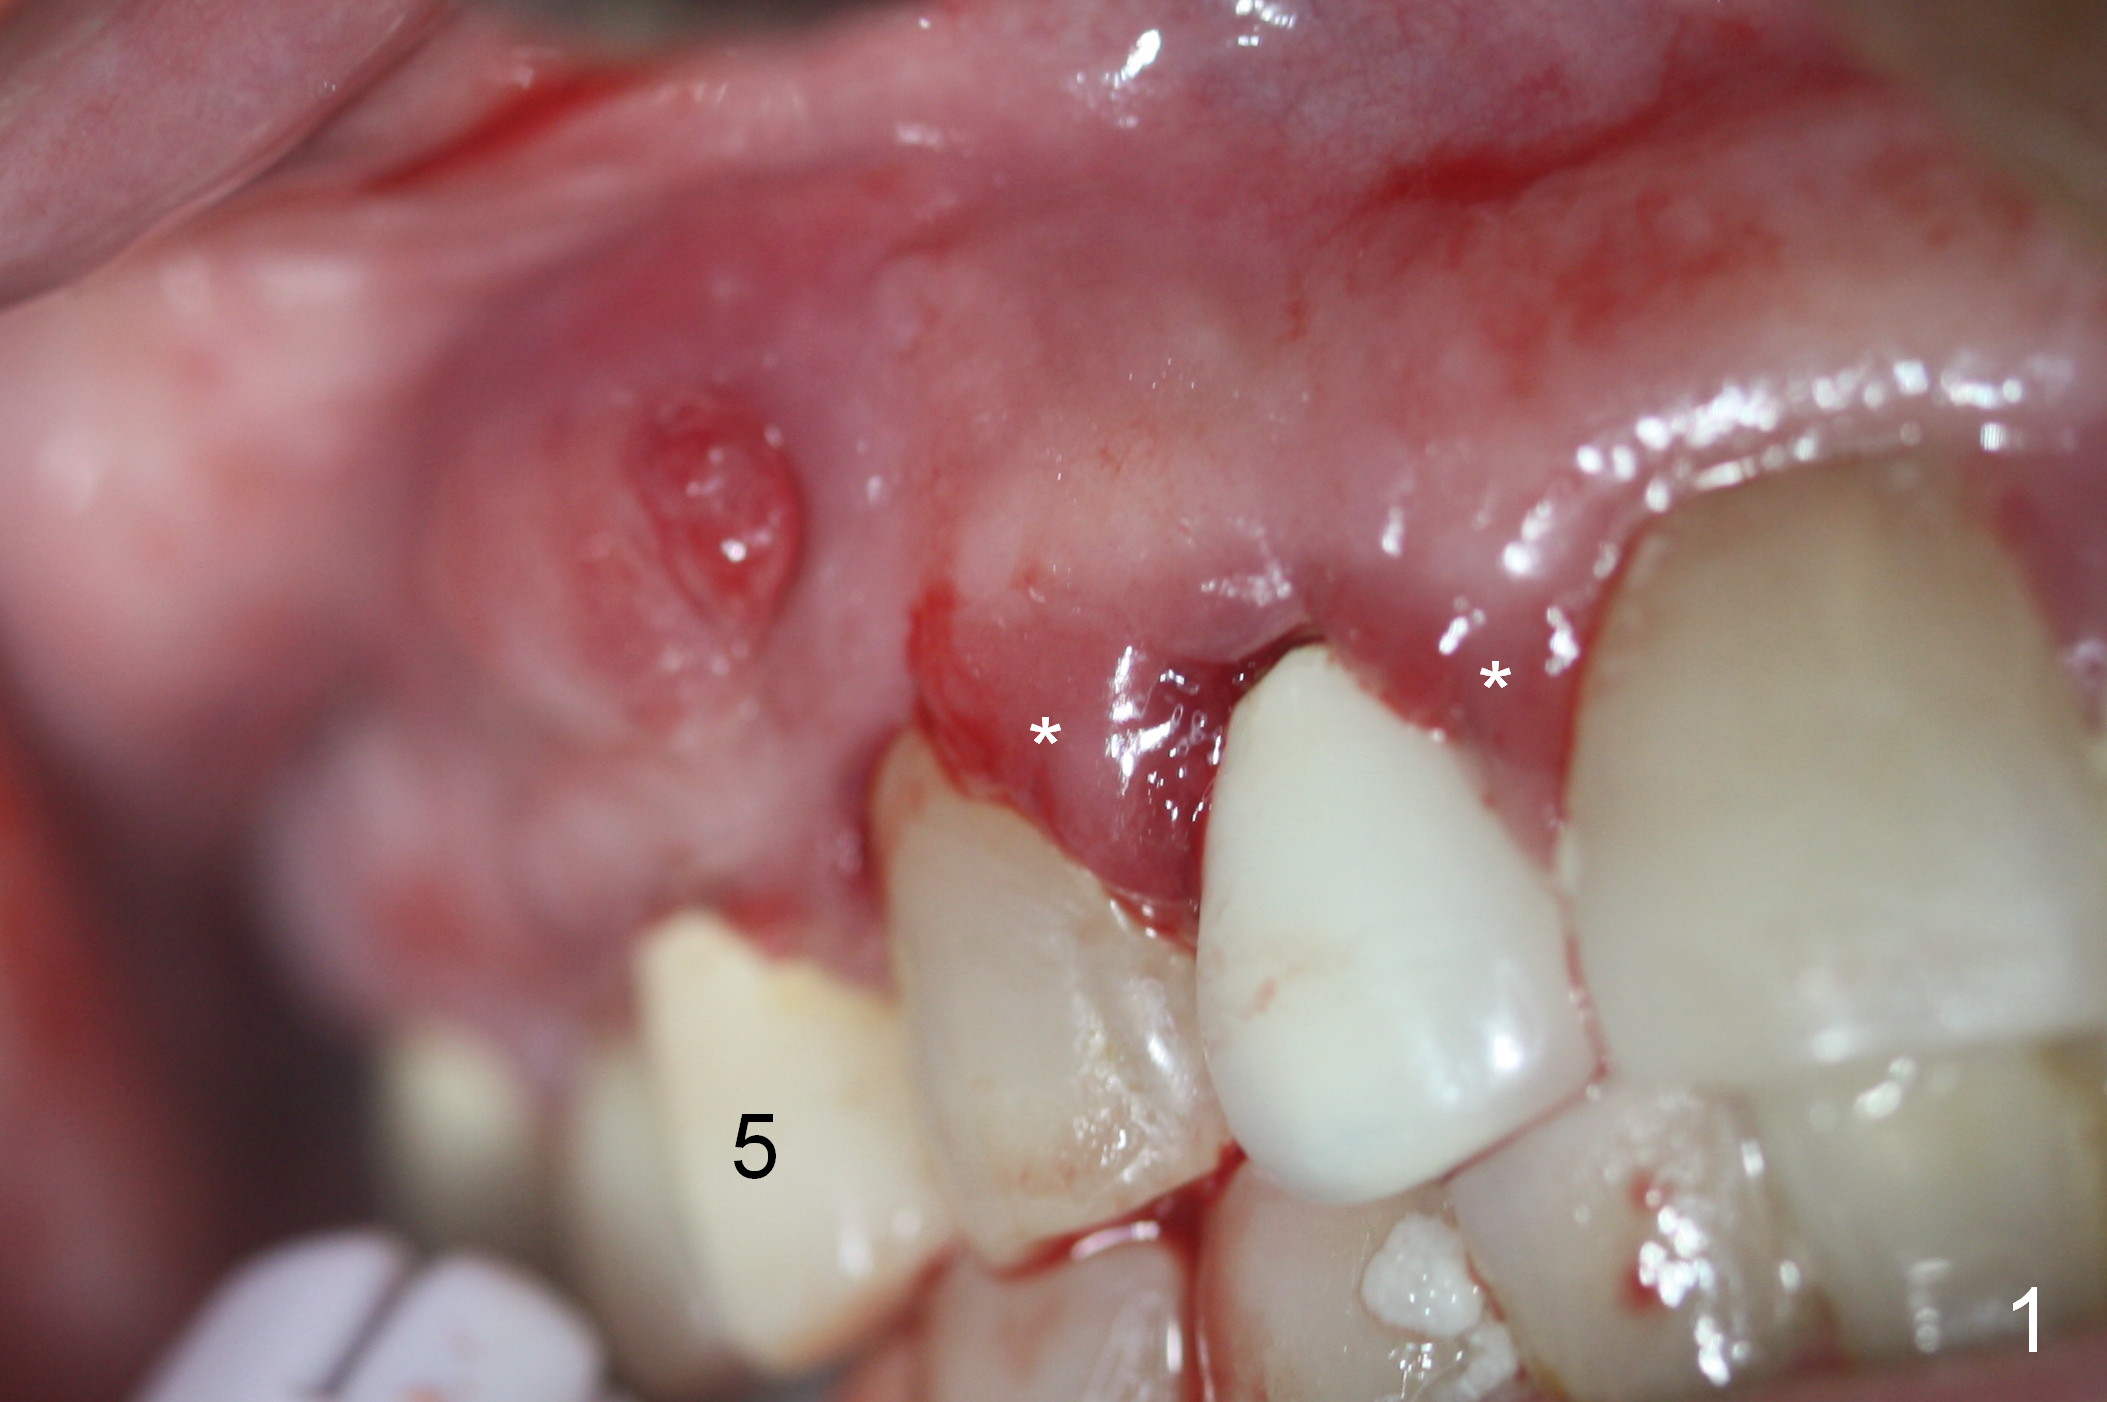

Preop photos show generalized gingival hyperplasia (hypertension med (Amlodipine, Calcium Channel Blocker), Fig.1 *), palatal (Fig.2<) and buccal (Fig.3 B) abscesses originated from the tooth #5. There is a smaller abscess buccal to the tooth #3 (not shown). After extraction, the buccal and palatal plates of the teeth #3 and 5 are found basically non-existent. When taps are placed, large socket defects are evident (Fig.4 *). In addition to sinus lift at #3 (Fig.5 black *), mineralized cancellous and cortical allograft (.5-1 and 1-2 mm) is placed around the implants with healing screws in place (white *). After the healing screws are removed and cemented abutments are placed, more allograft is packed (Fig.6-8 *). Closing the "dead" space in step may prevent immediately postop infection and peri-implantitis.